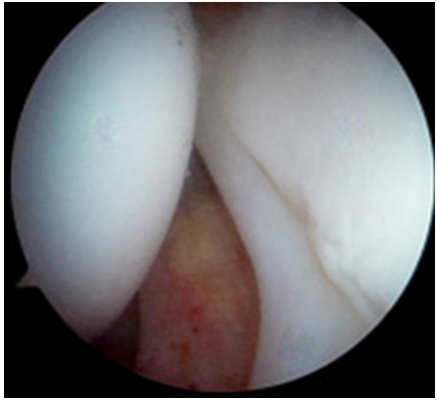

Nelle lesioni del labrum acetabolare è interessata la struttura fibrocartilaginea ad anello fissata al bordo del cotile. Il labrum può essere parzialmente danneggiato o lesionato nella sua intera superficie. Le lesioni sono spesso associate al conflitto femoro-acetabolare, ma possono anche essere isolate (natura traumatica o degenerativa). L'artroscopia d'anca permette la riparazione di tali lesioni fissando il labbro all'osso del cotile mediante il posizionamento di ancorette e punti di tensionamento (fig. 5).

Le lesioni cartilaginee interessano la cartilagine di rivestimento delle superfici articolari (fig. 6) e possono derivare da diverse condizioni patologiche (traumi, FAI non trattato, osteonecrosi etc.). L'artroscopia permette di valutarne l'estensione in maniera più accurata rispetto alla diagnostica per immagini e, in caso di lesioni non troppo estese, l'esecuzione di procedure mirate alla rigenerazione della cartilagine articolare.